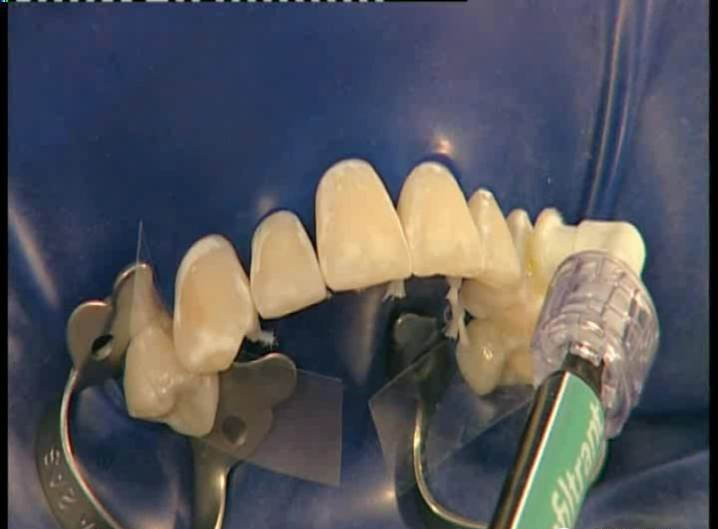

3、治疗部位涂布15%盐酸凝胶,酸蚀2分钟。2分钟后去除酸蚀剂,冲洗、干燥

dmg口腔材料怎么使用DMG-Icon专利之渗透树脂(内含操作视频)_https://www.jmylbn.com_新闻资讯_第8张